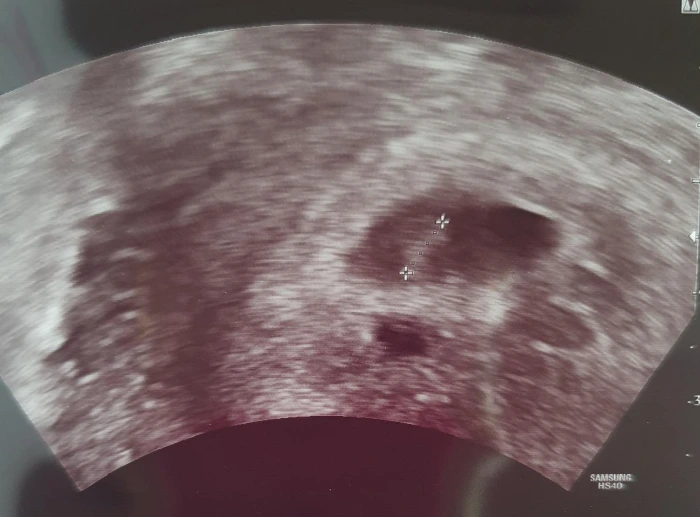

그렇게 일주일이 지나 처음으로 초음파로 반달모양의 아기집을 봤다.

사이즈도 적당하고 희미하게 작은 난황도 보인다고 했다. 난황은 계란으로 치면 노른자로 애기가 먹는 영양분이라고 간단히 설명을 들었다. 출산예정일도 나왔다. 2022년 1월 28일이란다.